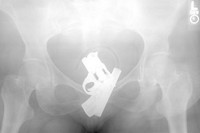

Tim bedah kandungan di sebuah rumah sakit panik saat foto sinar X menunjukkan ada pistol terjebak di vagina seorang pasien, dengan posisi seperti sudah terkokang dan siap ditembakkan. Operasi dilakukan dengan rompi antipeluru, tapi setelah dikeluarkan ternyata hanya korek gas yang bentuknya mirip pistol. (Foto: Neatorama)